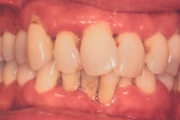

Krooniline parodontiit

Krooniline parodontiit on mikroobide poolt põhjustatud hammaste tugikudede põletik, mille tulemusena tekib progresseeruv alveolaarluu (nähtav röntgenograamil) ja periodontaalligamendi destruktsioon, igemetaskute moodustumine, igeme retsessioon või mõlemad kahjustused kombineeritult. Loe edasi »

- igemepiir on taandunud (3)

- hamba kinnitussidemete kadu (3)

- vahed hammaste vahel (5)